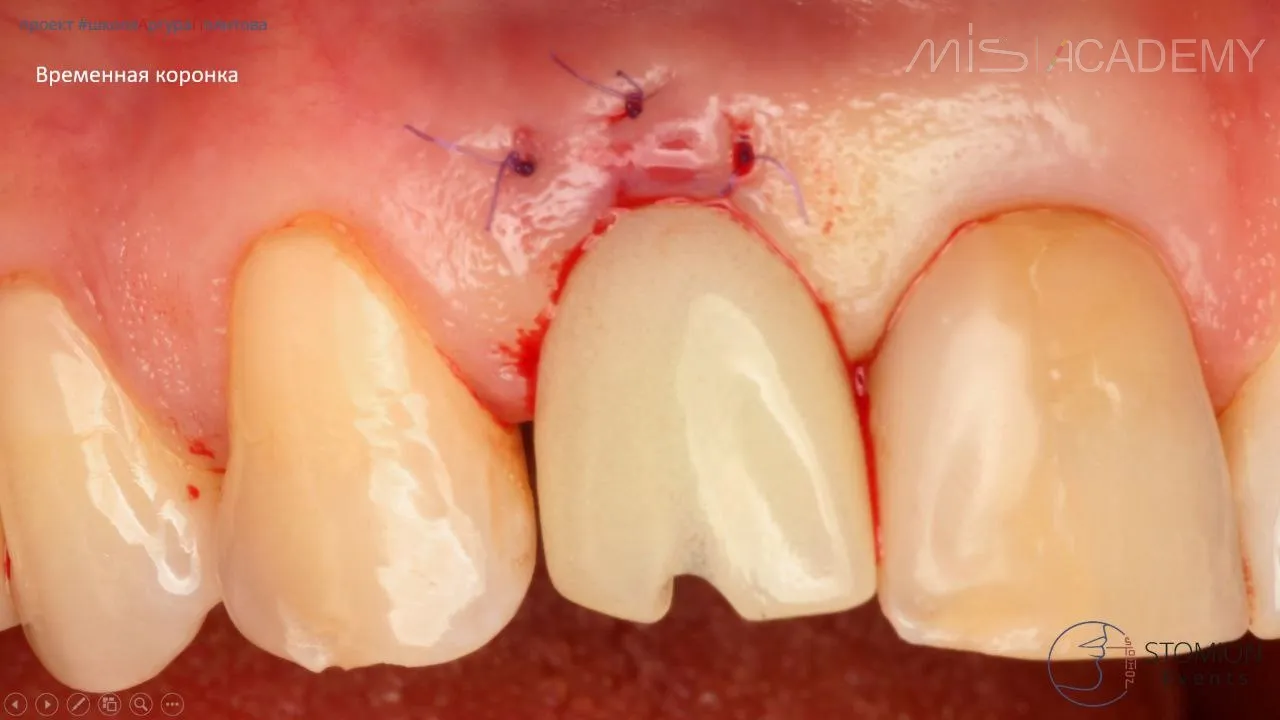

— По НХШ установлен имплантат MIS C1 3,3х13 (для получения торка), забор аутокости с бугра ВЧ, IDR, СТТ вестибулярно, коннект 3мм, немедленная нагрузка временной коронкой, изготовленной до операции, фиксация через позиционер.

— Спустя 6 месяцев изготовление постоянной коронки, цементная фиксация.